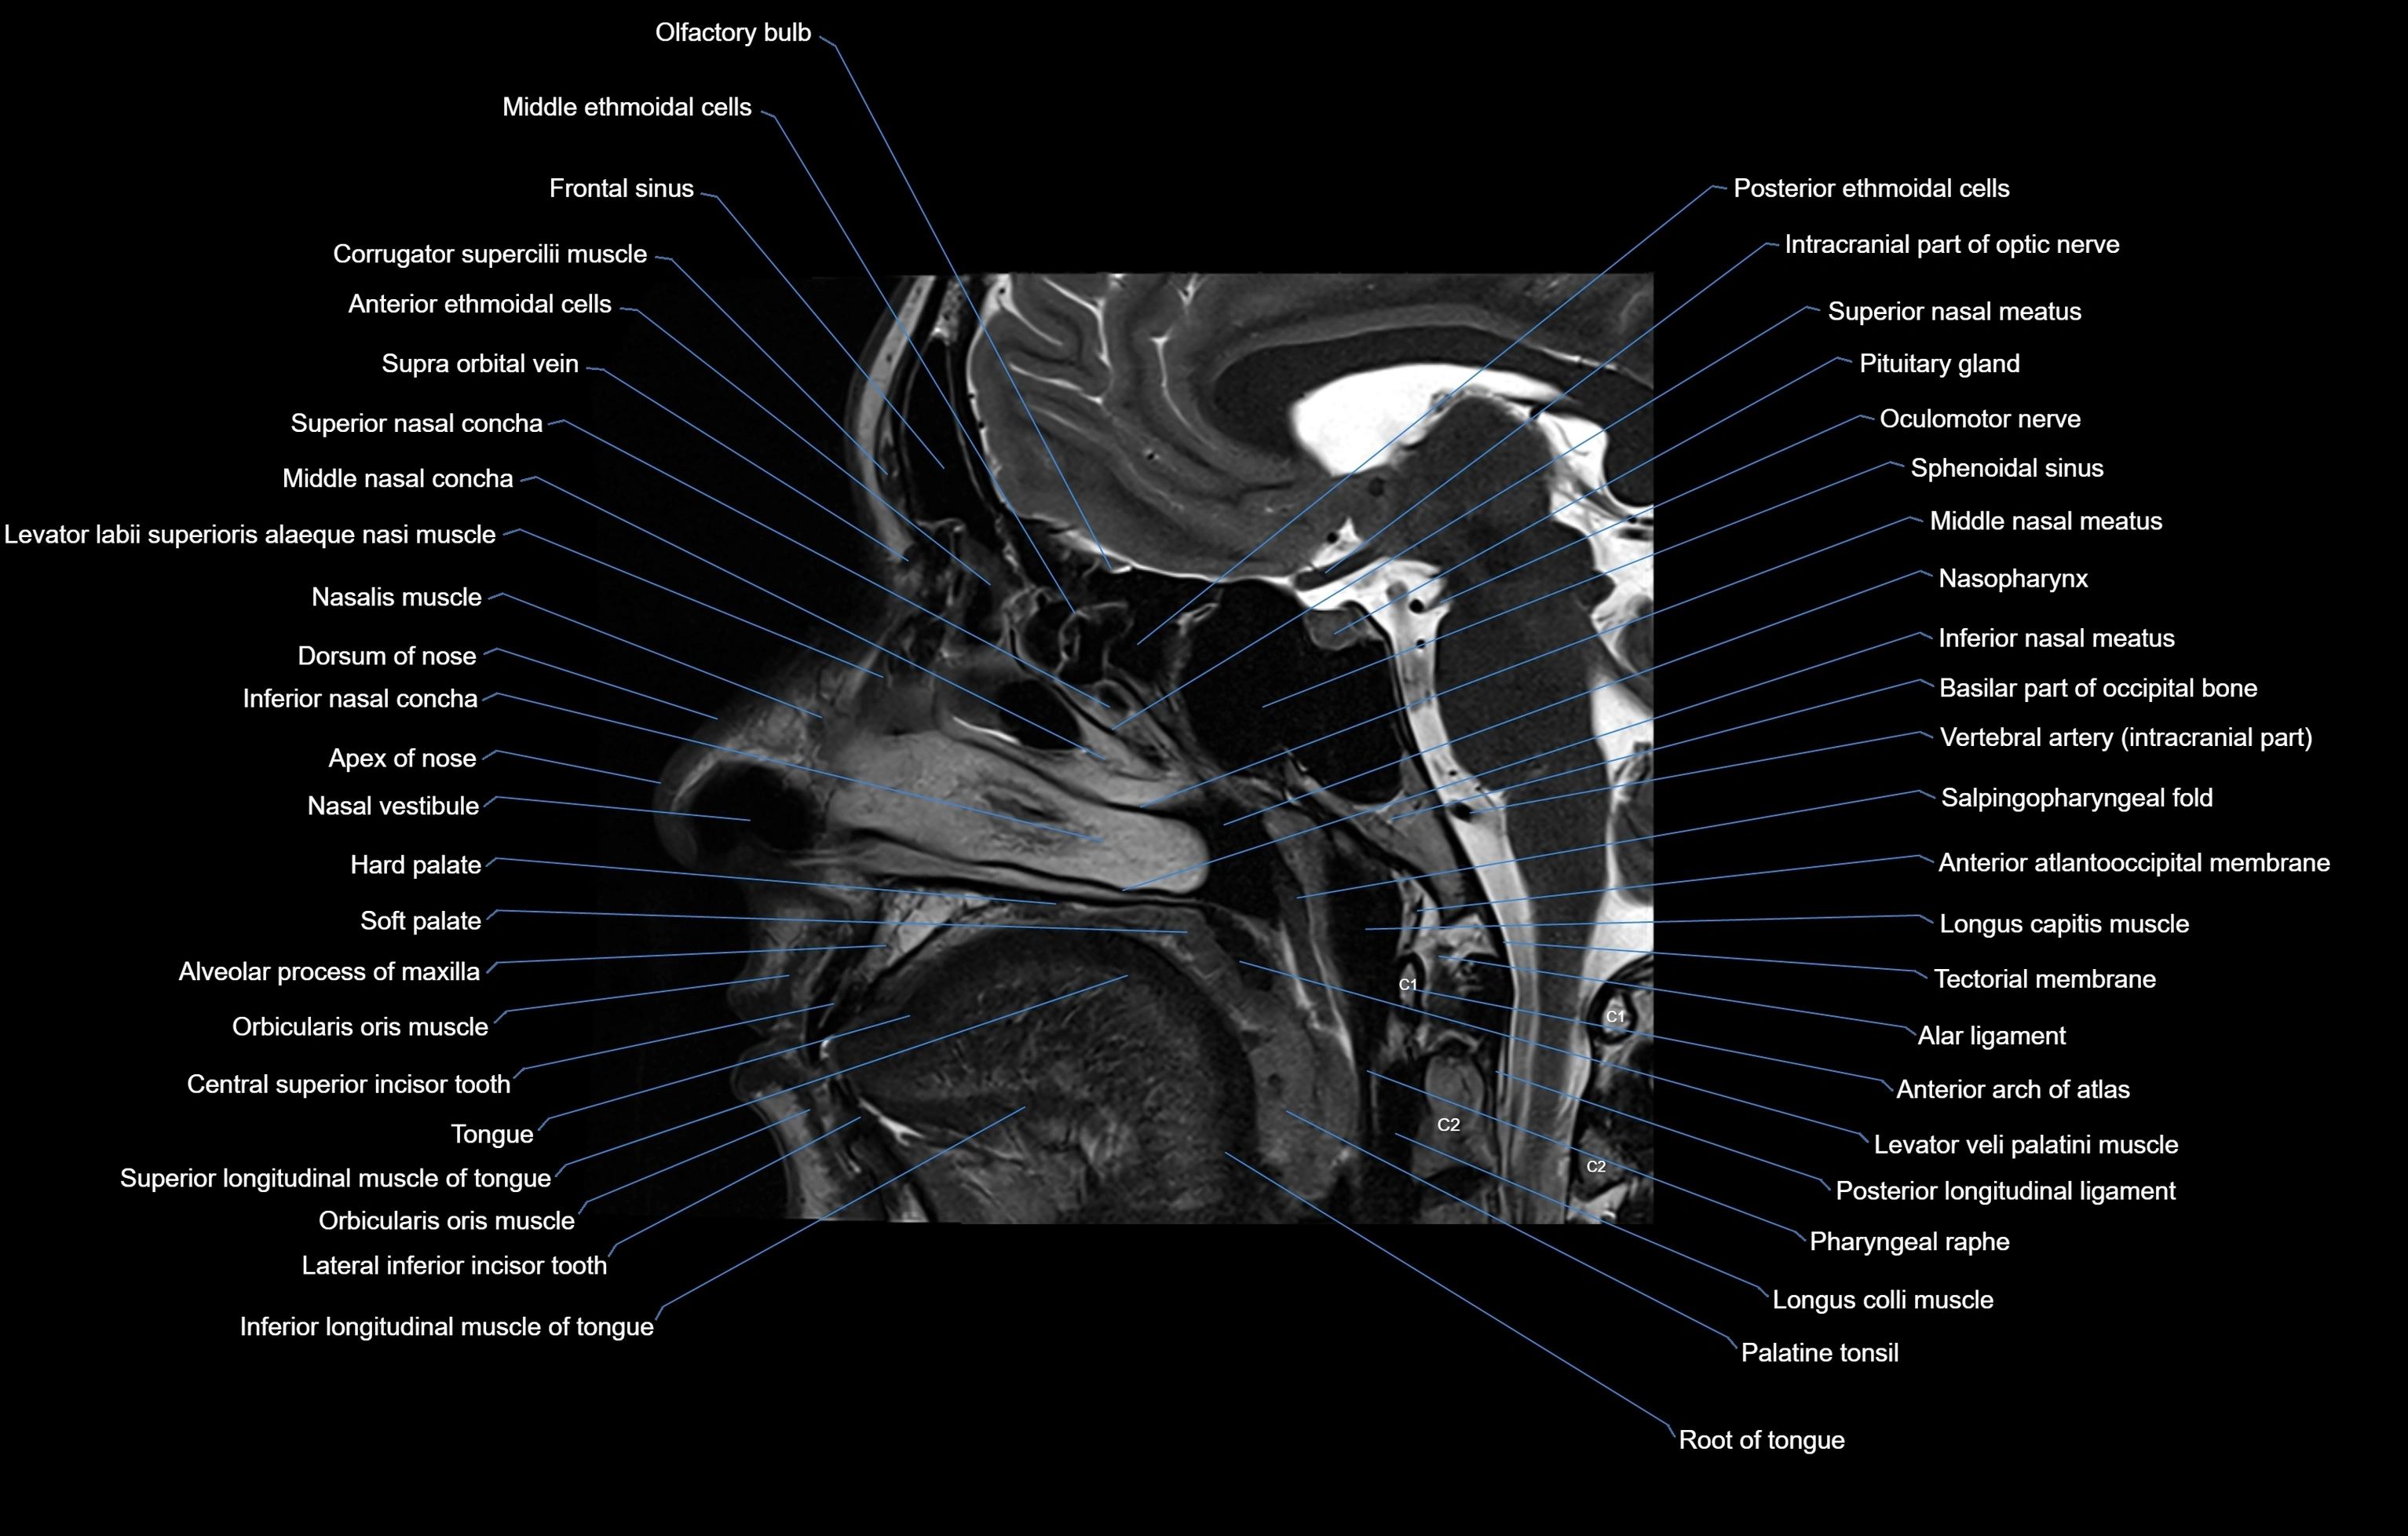

MRI images